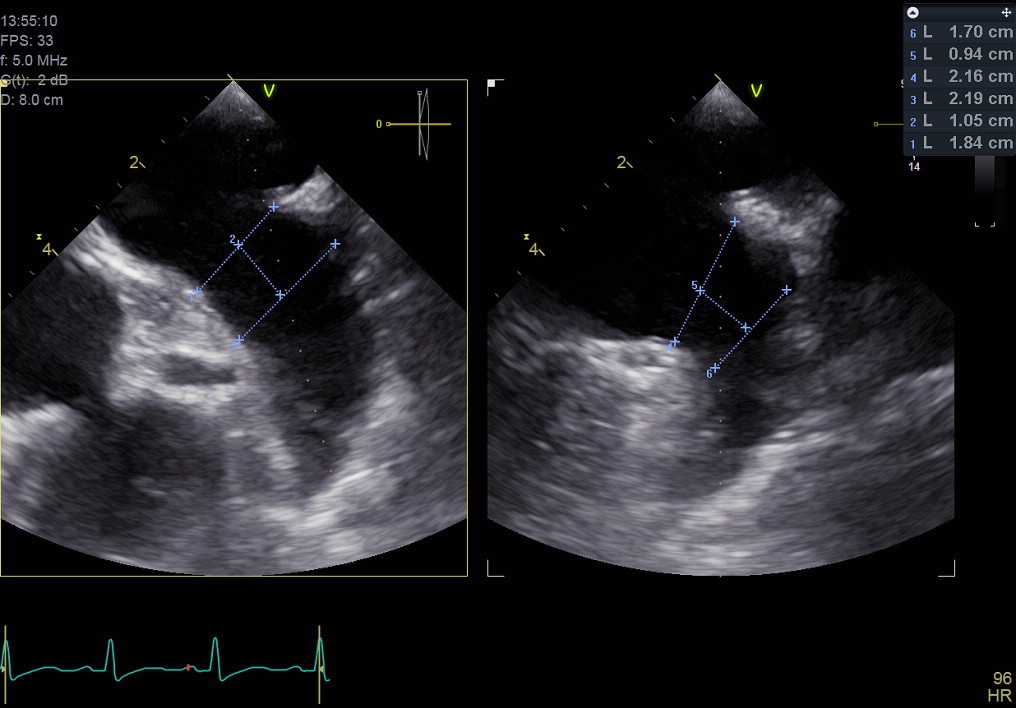

Coronary artery angiography showed only mild atheroscleorosis of left and right coronary arteriesWe used periprocedure transesophageal echocardiography to measure the size of left atrial appendage and we are going to place Lambree LAA closure systemTransseptal puncture was performed smoothly. LAA angio revealed ostial diameter was 17.3-25.3mm (diastole, systole). Landing zone diameter was 18.2-20.7mm.